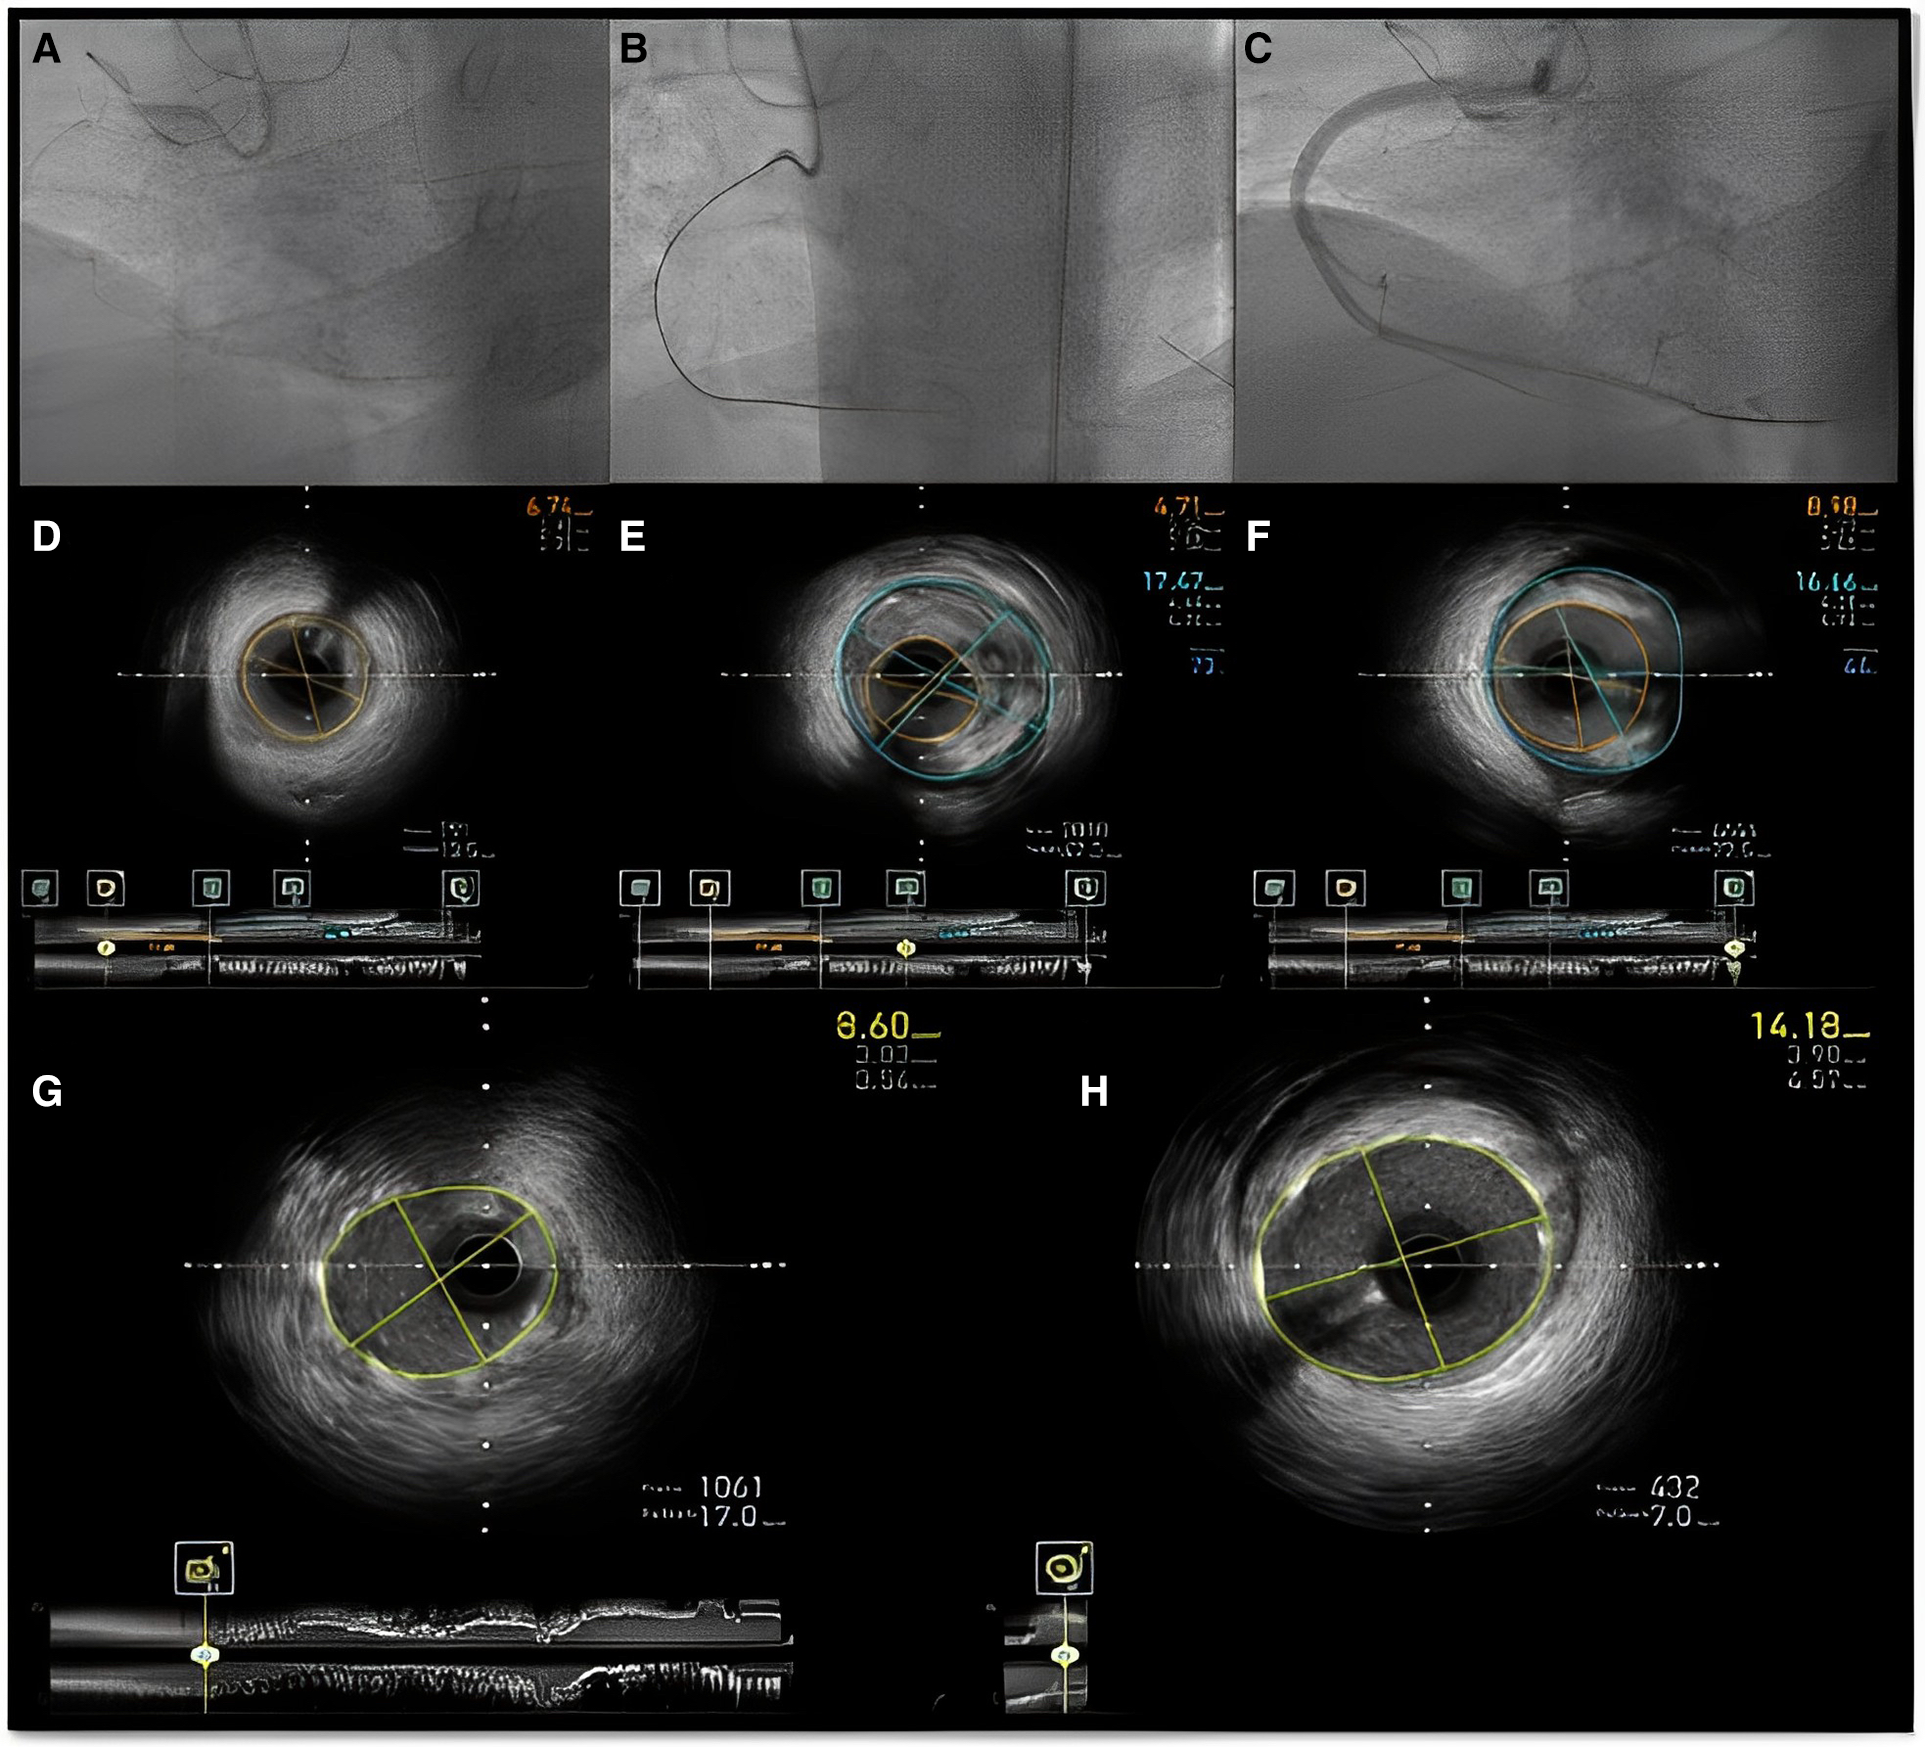

Figure 9

Figure 10

Intravascular imaging (IVUS) guided chronic total occlusion (CTO) percutaneous coronary intervention; (A) initial angiography with contralateral injections to define CTO lesion characteristics; (B) successful antegrade wire crossing; (C) final angiographic result after IVUS guided drug eluting stent (DES) implantation; (D) distal landing zone with reference cross sectional area and diameter estimated at 3 mm; (E) CTO segment cross-sectional area and reference diameter estimated at 4.5 mm; (F) proximal landing zone with reference cross sectional area and diameter estimated at 4.5 mm. The overall lesion length requiring stent coverage from distal landing zone was estimated at 65 mm and therefore two overlapping DES 3.0 × 38 mm and 4.0 × 38 mm were successfully implanted and post-dilated with 3.5 and 4.5 mm non-compliant balloons based on media to media reference diameters as per IVUS measurements; (G) distal stent cross-sectional area with excellent absolute (>5.5 mm2) and relative expansion (>100%); (H) proximal stent cross-sectional area with excellent relative expansion (>100%). Used with permission by Elsevier. Kalogeropoulos AS, Alsanjari, O, Davies, JR. et al. Impact of Intravascular Ultrasound on Chronic Total Occlusion Percutaneous Revascularization. Cardiovasc Revasc Med. 2021; 33:32–40.